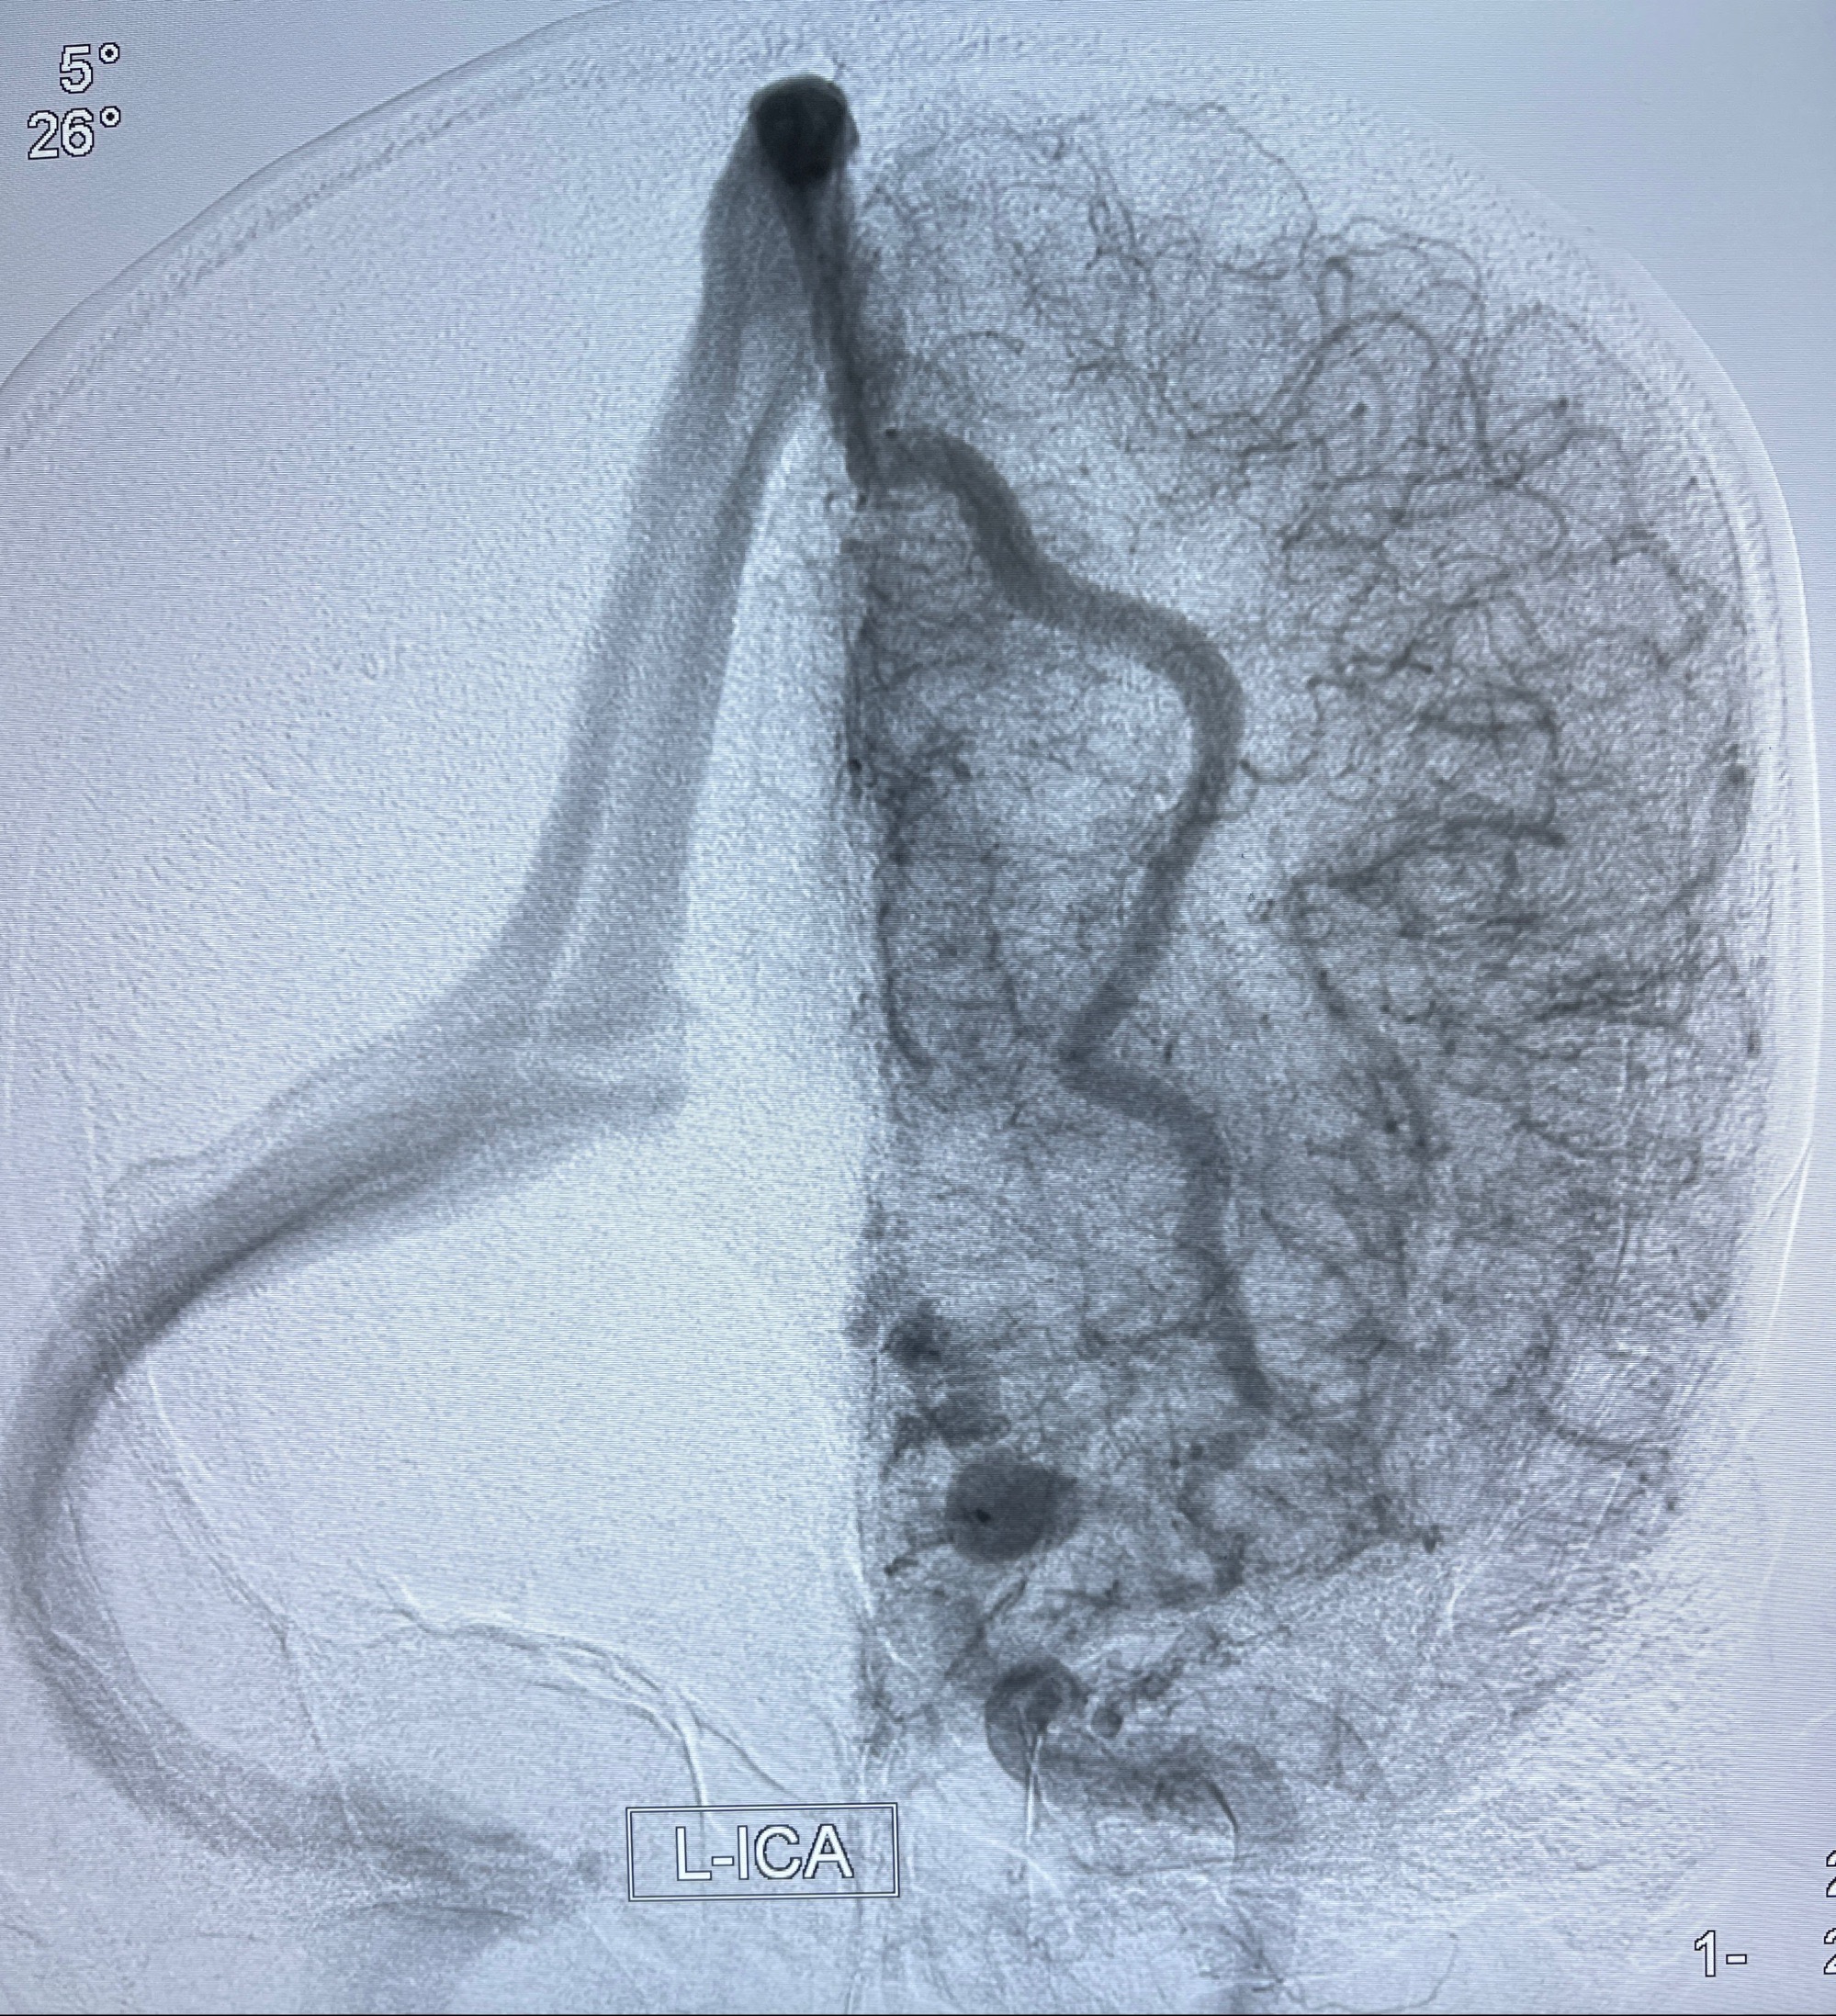

2023年8月21日]景德镇市第一人民医院脑血管造影检查,提示:主动脉弓、双侧颈总动脉、锁骨下动脉造影未见异常,左侧大脑前动脉静脉瘘。

2023-09-13全脑血管造影:前颅底硬脑膜动静脉瘘,供血动脉为双侧胼周动脉、眼动脉脑膜支,静脉向上矢状窦方向引流